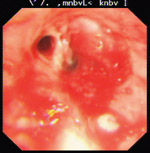

2、內窺鏡檢查可以有效地發現狹窄的氣管和支氣管病變。

(5)支架移位 主要由於用力咳嗽或在氣管插管時發生,另外可能是支架型號偏小而不能牢固固定於適當部位。支架置入術後要定期進行胸部X線檢查或纖支鏡檢查,觀察支架置放情況。若患者出現支架移位,可經再次纖支鏡下取出並置入合適支架。

(6)支架腔內肉芽和腫瘤組織生長 增生的組織通過支架網眼向支架腔內生長,形成新的氣道狹窄,尤其是在繼發感染的情況下更易形成肉芽。因此術後應加強病情觀察,特別是觀察體溫、呼吸的變化,咳嗽咳痰情況,有無痰中帶血及呼吸困難。患者出現支架腔內腫瘤組織生長,在纖支鏡下進行微波燒灼處理。